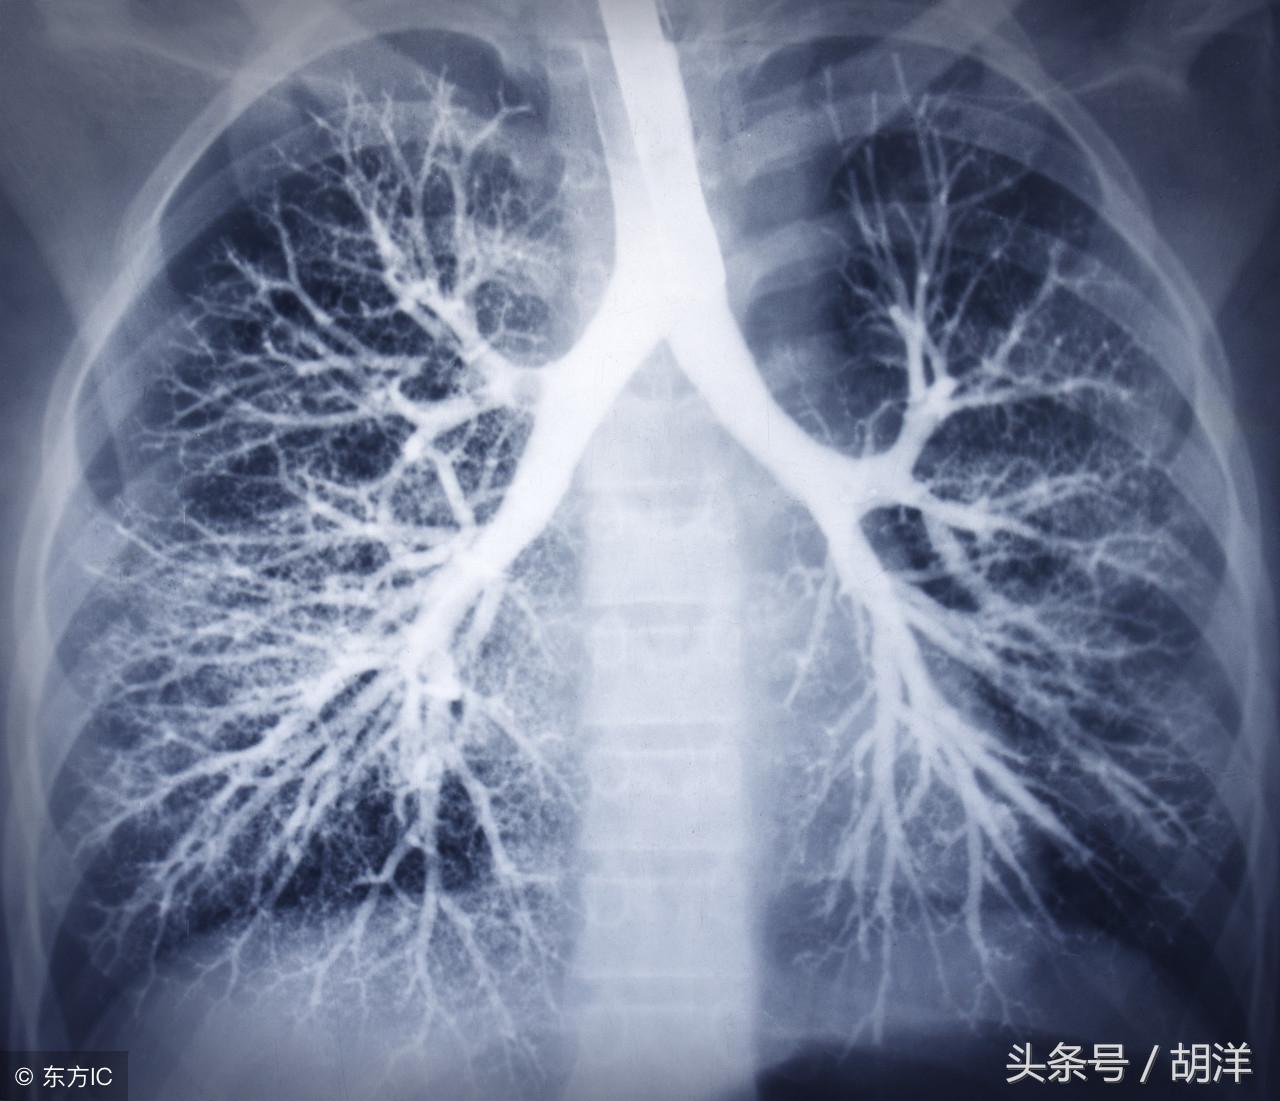

咳血又称咯血,是呼吸科一个比较严重的症状,由于其可能提示肺部肿瘤等严重疾病而受到重视,但事实上在引起咯血的病因中,肺部恶性肿瘤所占的比例并不是很大,但很多人因咯血而焦虑异常,特别是咯血久治不愈情况下,更加令人无法正常的生活和学习,那么哪些疾病可能导致反复发作痰中带血或者咳出满口鲜血呢?

支气管扩张是一种支气管管壁结构破坏性疾病,正常情况下,支气管是一个带有弹性,拥有一定管径的能够维持正常呼吸通气的结构,当管壁结构受到破坏时,气管会受到被动的牵拉而扩张,管壁的血管由于弹性较小,容易被撕扯呈血管瘤改变,一旦胸腔内血流压力增大可能冲破血管瘤变薄的管壁而导致大咯血,少量渗血时则呈现为痰中带血。

曲菌球

曲霉菌是一种常见的真菌,正常情况下,曲菌很少感染肺部结构正常,免疫力良好的人群,当肺部受到破坏,特别是形成较大空洞和支气管扩张时,曲霉菌可以趁机进入空洞扩张的支气管内与其中渗出的白细胞、纤维素等成分形成球状结构,成为曲菌球,曲菌球在空洞内能够自由的活动,对空洞壁有机械性的损伤,当损伤到管壁变异的血管瘤时,极有可能导致大出血。